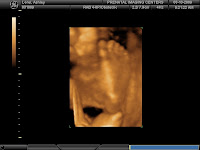

Well, we are on the home stretch and so ready to meet the little guy! Things are going well. I am definitely growing by the day and have gained 20 lbs as of my appointment last Thursday. Baby Lorei should weigh around 4-5 lbs at this point. I am growing by the day as you can see below. Everything is getting more difficult to do now! We had our childbirth class last weekend and feel we are as ready as we can be for the big day! Ryan's parents got us the car seat, adaptors and stroller, so we are going to install the car seat adaptors this week. Thanks so much Lois and Glenn!!